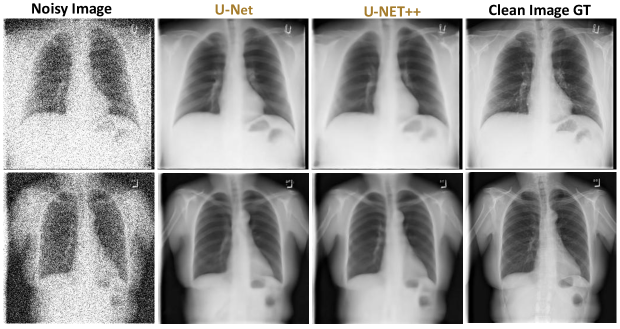

To qualitatively assess image reconstruction fidelity, we compare denoising outputs at 10%, 20%, and 30% Gaussian noise levels using representative test samples. Each comparison (Done under 1-GPU configurations) includes the noisy input, U-Net output, U-Net++ output, and the clean ground truth.

Figures 56, and 7 illustrate results at 10%, 20%, and 30% noise levels, respectively.

At 20% noise (Figure 6), U-Net begins to blur finer anatomical details. Mediastinal contours and soft gradients become less distinct. U-Net++, however, maintains better spatial consistency across lung lobes and diaphragm curvature. Noise artifacts that appear in the lower lobes under U-Net are largely suppressed in U-Net++, which retains soft tissue definition.

Figure 6: Visual comparison of noisy input, U-Net and U-Net++ denoised outputs, and ground truth (20% noise levels).